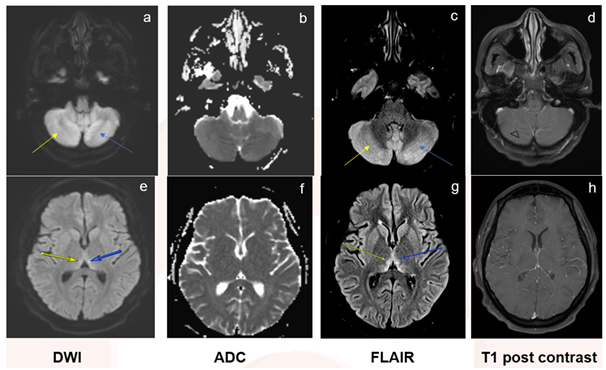

She had extensive workup for a deteriorating neurologic exam and mental status with significant weight loss. She had mildly elevated inflammatory markers including c-reactive protein (2.86mg/dL, ref <0.50) and erythrocyte sedimentation rate (68 mm/hr, ref<32). The electroencephalogram showed diffuse slowing without any epileptiform discharges or seizures. The cerebrospinal fluid (CSF) showed 2 cells (ref 0-5/uL), 48 glucose (ref 40-75mg/dL) and 31 protein (ref 15-45 mg/dL) with negative cytology and cultures and polymerase chain reaction (PCR) was negative for mycobacterium TB. CSF angiotensin converting enzyme (ACE) was within normal limits and CSF paraneoplastic panel was unremarkable. Serum voltage gated potassium antibody, however, was elevated (207pmol/L, ref<31).Magnetic resonance imaging of the brain showed bilateral cerebellum and thalami edema with cerebellar folia enhancement concerning for cerebral tuberculosis and paraneoplastic encephalitis (Figure 1). Imaging of the spine was unremarkable.

Figure 1 Shows hyperintensity in the bilateral cerebellum and thalami concerning for edema (a-c, e-g, ) and cerebellar folia enhancement (g, )..